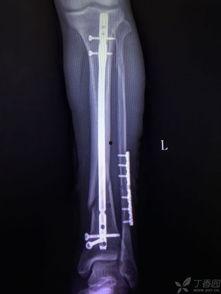

首先,让我们来认识一下髓内钉。髓内钉,顾名思义,就是一根插入骨髓腔内的金属钉子。它主要用于治疗长骨骨折,如股骨、胫骨等。髓内钉的优点在于,它能够有效地固定骨折部位,促进骨折愈合,同时减少手术创伤。

2. 手术过程:手术过程中,医生会在骨折部位切开皮肤,找到骨髓腔。使用特殊的工具将髓内钉插入骨髓腔,直至钉子的另一端露出骨折部位。

3. 固定骨折:在髓内钉插入骨髓腔后,医生会使用连接杆将钉子的两端连接起来,从而固定骨折部位。

2. 固定效果好:髓内钉能够有效地固定骨折部位,促进骨折愈合。